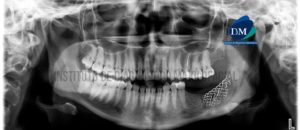

Paciente de sexo masculino de 18 años de edad acude al Instituto de Diagnóstico Maxilofacial para evaluación de terceras molares por motivo de exodoncia. A